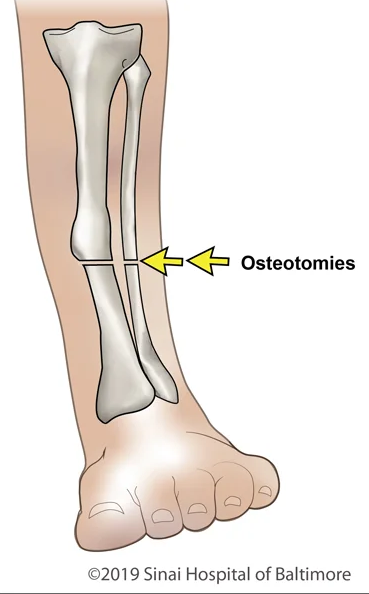

断骨断骨,顾名思义就是把股骨或胫骨切断,然后把可调节的金属钉插进去。

这个既灵活又坚固的玩意儿,可以通过遥控器调节长度。

根据骨骼平均生长速率,医生一般会以每天1mm的长度来调节金属钉。

为了进一步减少损害,这一天1mm,还得分成三到四次来拉伸,突出一个稳健。

说起断骨增高,其实初衷是为了治疗肢体有缺陷的人。

比如有的人左脚比右脚短,或者腿部畸形,都可以用断骨的方式来矫正。